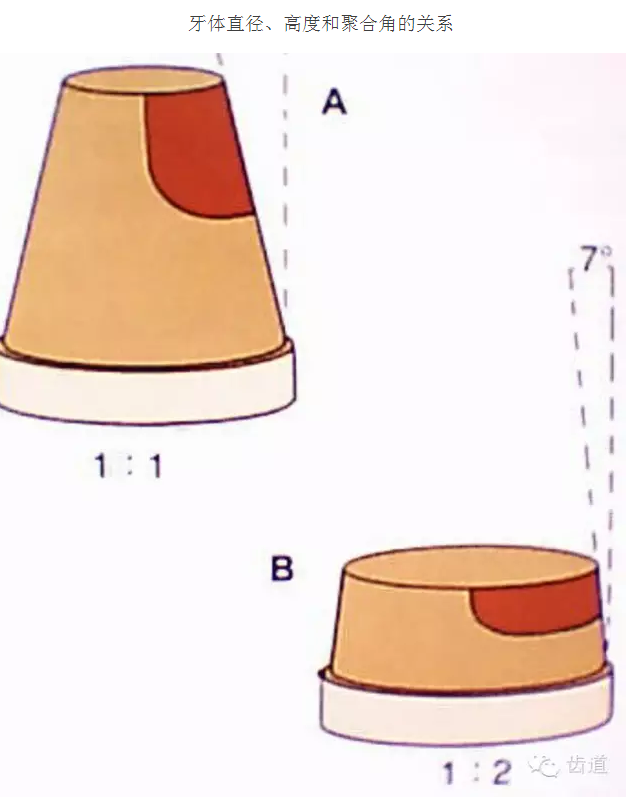

牙的外形及洞形的幾何形狀:主要是牙體制備出一定聚合角度產(chǎn)生的阻擋作用